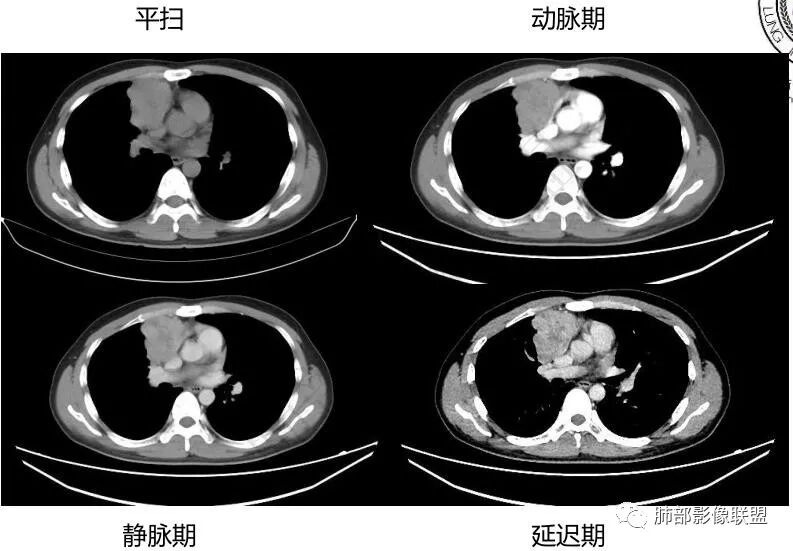

中青年男性,前纵膈偏右侧软组织肿块,形态不规则,有分叶,密度均匀,增强病灶轻中度强化,内部可见低或无强化区域,病灶与血管周围间隙分界不清晰,考虑恶性或交界性肿瘤,胸腺类癌>生殖细胞瘤>淋巴瘤。

青年男性,前上纵隔占位,渐进强化,坏死不明显,nse稍高,首先考虑类癌,鉴别精原,内胚窦瘤,需要结合实验室检查HCG,AFP等

中年男性,胸痛,既往健康,前上纵隔软组织肿块,形态不规则,密度不均,没有血管包埋及受侵征象,呈不均匀强化,考虑胸腺瘤,鉴别淋巴瘤,精原细胞瘤,胸腺癌

前纵隔右侧见大肿块,边缘清,同侧内乳动脉增粗,渐进性延迟强化明显,强化密度不均匀,中心见偏低密度灶,上腔静脉内后侧推压移位(提示肿块质地偏硬),副神经节瘤,与巨淋巴细胞增生症鉴别。

青年男性,咳嗽,右上前纵隔不规则肿块,分叶,上腔静脉受压,内乳动脉增粗,延迟强化明显,坏死不明显,考虑来源纵隔,胸腺瘤,淋巴瘤,神经源性肿瘤都可以,比较年轻,猜个淋巴瘤吧。神经源性肿瘤代排。

青年男性,前纵隔软组织肿块,偏右侧生长,边缘多发分叶,包绕临近血管生长,增强后轻度强化,并呈渐进性,可见点状坏死,考虑胸腺瘤,鉴别淋巴瘤,生殖细胞肿瘤,巨淋巴结增生症

青年男性,前纵隔偏右侧软组织肿块,密度均匀,分叶,渐进性不均匀强化,可见点状坏死,考虑胸腺瘤,鉴别生殖细胞肿瘤,淋巴瘤,CD。

青年男性,前纵隔偏右侧肿块,分叶,与邻近血管分界不清,上腔静脉受压,不均匀渐进强化,点状坏死,考虑胸腺瘤,鉴别胸腺类癌

男性32岁前纵隔偏右侧见一不规则软组织影,边缘毛刺,呈分叶征,同侧内乳动脉增粗,延迟性强化,内见条状分隔影,考虑胸腺瘤(B1、2,临界年龄段,分隔有些提示倾向),NSE轻度升高,中度强化,类癌代排。内胚窦及精原等生殖细胞肿瘤影像不符合,建议结合实验室检查

年轻男性,NSE稍高,前纵隔偏右侧不规则实性肿块,平扫密度均匀,增强渐进性不均匀强化,内见低密度区,似见条样分隔。考虑为胸腺瘤,建议实验室检查HCG,AFP等鉴别生殖细胞肿瘤

青年男性,前上纵隔占位,偏侧生长,边缘不规则,可见分叶及分隔,内见少量无强化低密度区,常规考虑胸腺瘤,NSE稍偏高一点,会不会是实验室误差?

前纵隔右侧不规则软组织肿块,边缘欠清,增强渐进性强化,内见星状无强化分隔,部分分隔延迟强化,青年男性,首先考虑精原细胞瘤,鉴别胸腺瘤,NSE轻度升高,类癌也需鉴别!

前纵隔肿块,轻度分叶,边界不清楚,延迟强化,可见分隔,倾向恶性或具有一定侵袭性病灶。

一.精原细胞瘤  20-40岁 ,年轻男性多见,密度均匀,边界清楚,轻度强化,可有坏死,基本不出现钙化,HCG可升高,AFP一般不升高,侵犯血管的程度一般比淋巴瘤明显。

二.纵隔淋巴瘤 青少年(20-30)老年(60-80)两个高峰年龄段,男性略多。软组织肿块,常有多结节融合感,边缘较光整,少见分叶。跨间隙,跨中线生长,常见周围淋巴结影,治疗前较少钙化,少见胸膜及心包结节。淋巴瘤常往血管间隙生长,包绕临近大血管,而血管受侵犯较轻,多为轻中度强化,幅度大于30Hu。

三.高危型胸腺瘤 年龄偏大,以中老年多见,中度或明显强化,强化幅度大于淋巴瘤,有囊变和坏死,可见钙化,胸膜转移,三分之一有重症肌无力,尤其是B2-B3型等。胸腺癌可见淋巴结转移。